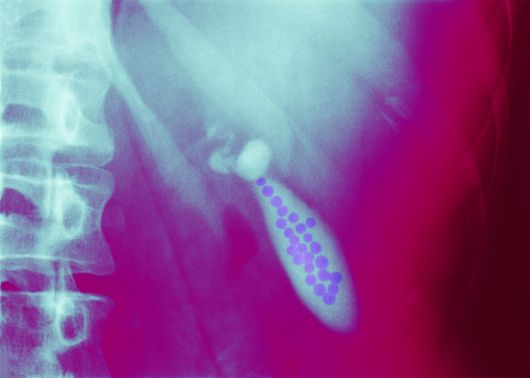

복부 초음파 사진 속 담낭 내부에 작은 담석들이 무리 지어 형성된 모습. 담석은 방치 시 통증과 염증의 원인이 된다. 사진=게티이미지뱅크. |

담낭(쓸개)은 간 아래에 있는 약 10cm 크기의 작은 주머니 모양 기관이다. 이 기관은 원래 간에서 만든 담즙(쓸개즙)을 저장했다가 음식물 섭취 시 분비해 지방의 소화와 흡수를 돕는다. 하지만 담즙 성분의 균형이 깨지면 내용물이 딱딱하게 뭉치며 담낭이나 담도에 결석(담석)이 만들어진다. 담석은 초기 증상이 없다가 담관을 막는 순간 극심한 통증과 합병증을 유발한다.